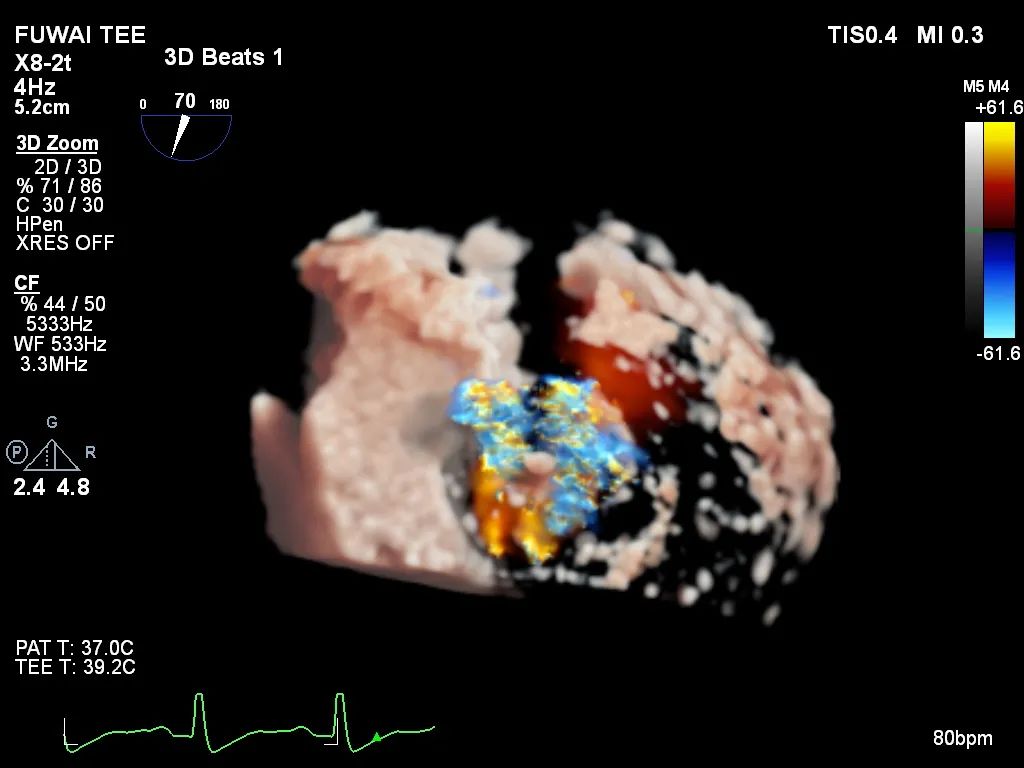

手术团队使用MitraClip®独特的三层双调弯导管,经股静脉穿刺,在食道超声引导下完成房间隔穿刺。穿刺后将导管送入左心房,对准二尖瓣目标位置P2区域。准确捕捉瓣叶,二尖瓣夹释放后,超声显示反流几近消失,患者各项生理指标正常,手术顺利完成。